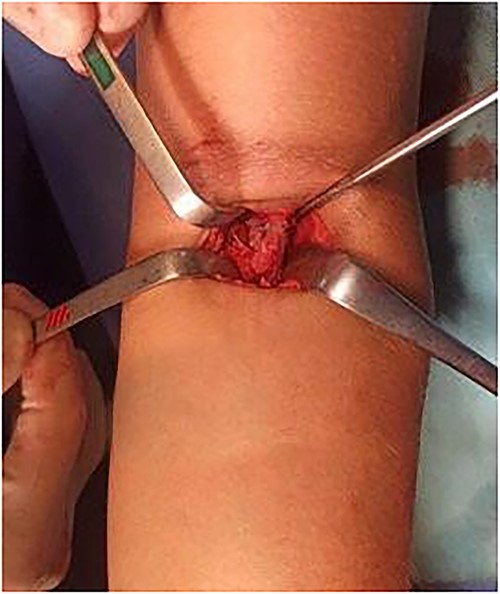

Given this clinical presentation, surgical treatment was recommended for tendon repair. A single-incision technique with fixation using two suture anchors was employed (Figs 5 and 6), following the method described by Maciel et al. [13]: An ~5 cm access incision was made in the anterior region of the proximal third of the forearm in a transverse plane. With the forearm in complete supination and at a 10-degree elbow flexion, two suture anchors were positioned, loaded with high-strength threads, into the radial tuberosity. Fixation of the distal anchor repair was performed first to establish tendon length, followed by fixation of the proximal anchor repair to maximize the tendon-to-bone contact area. Intradermal skin suturing performed.